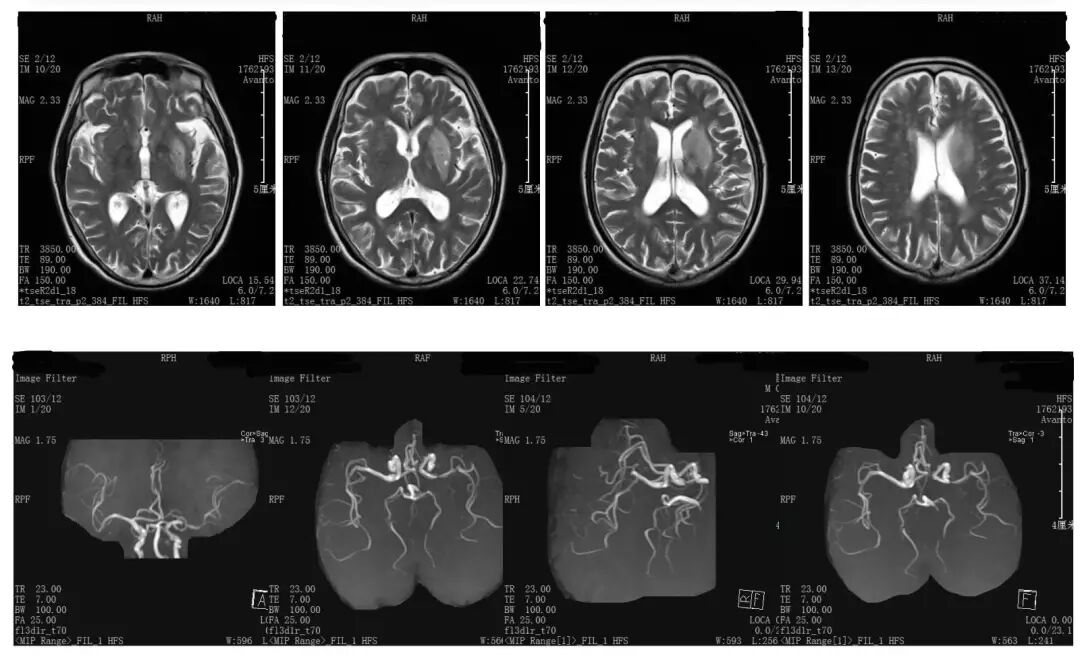

◆ 诊断影像:

CT平扫未见早期梗死表现;CT灌注成像示:左侧半球MTT延长,CBF见内囊有部分核心坏死,CBV下降不显著。

影像表现与评分不符,图像经MIStar处理后,左侧CBV核心区为4ml,半暗带>15ml。

CTA示左侧颈内动脉起始部闭塞,ICA末端显影,大脑中动脉M1闭塞。